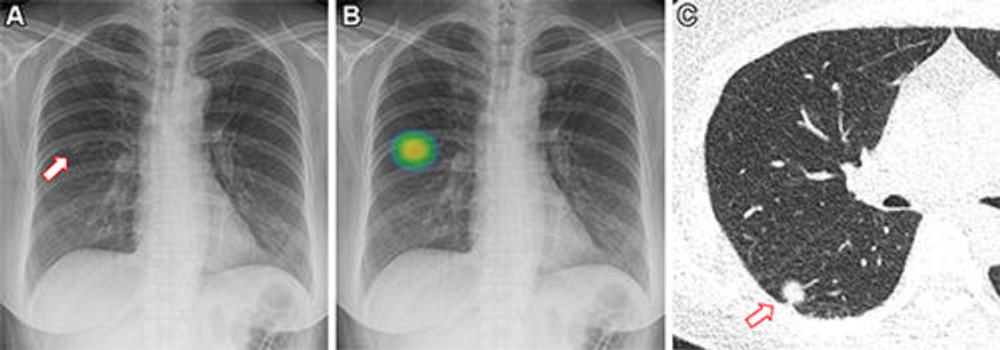

Figure 3. Images in a 60-year-old woman who underwent chest radiography for health checkup purposes and was allocated to the artificial intelligence (AI) group. (A) Frontal chest radiograph shows a subtle nodular opacity (arrow) in the right middle lung zone. (B) The lesion was detected by the AI-based computer-aided detection software, with an abnormality probability of 81.1%. The designated radiologist reported this chest radiograph as positive. (C) Axial, noncontrast, low-dose chest CT scan shows a 1.1-cm solid nodule (arrow) in the right lower lobe. The patient underwent percutaneous needle biopsy, and the nodule was confirmed to be adenocarcinoma.